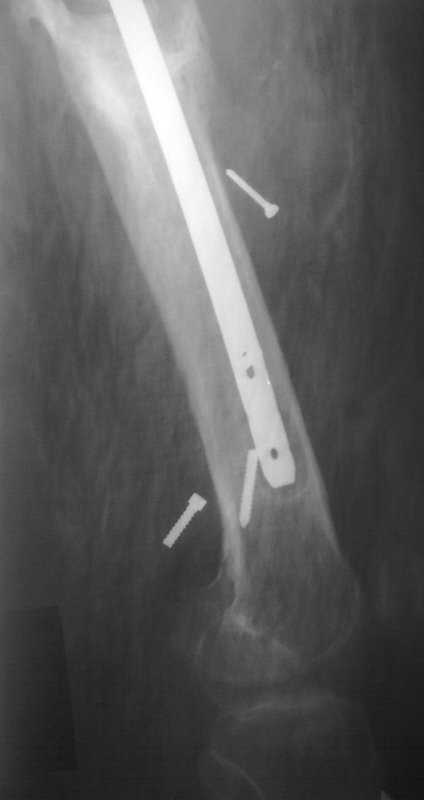

Здравствуйте уважаемые коллеги, прошу Вашего мнения относительно тактики лечения пациента М. 37 лет, рост 170 см. вес 140 кг. Анамнез: пострадал в рез. ДТП в 2004 году, лечился в одной из районных больниц гдебыл прооперирован DCP. в 2006 году перелом м/фиксатора с последующим реостеосинтезом стержнем Кюнчера без блокирования. в 2007 году перелом фиксатора после чего обратился в нашу клинику, где было произведено удаление гвоздя, БИОС L-360 mm D-12 mm с кортико-спонгиозной пластикой, в теч. 6-и мес. больной был под наблюдением динамизация ч-з 2 мес. после чего пациент исчез с поля зрения. Появился с жалобами на болезненность в месте перелома, укорочение ноги, в течении года поочередно в ягодичной области и н/3 бедра функционирующие свищи. На данный момент имеем свищ в н\3 бедра, укорочение ноги на 3 см, внешняя ротация.Произведена фистулография, взят посев из свищевого хода. Планируется: - Удаление м\фиксатора и всех винтов(за исключением проксимального) - I&D с рассверливанием до 16 мм. - кортикотомия, открытое устранение деформаций - БИОС стержнем L-360 mm D-12 mm с а.б. покрытием - бусы с ванкомицином в области свищей

Уважаемый Илья! Если я правильно понял, фистулография у Вас - вторая картинка, а ранки на первой фотографии в области нижних блокирующих винтов и приблизительно на уровне псевдоартроза. Хотелось бы уточнить, есть ли клинические проявления свища на уровне псевдоартроза, отделяемое и т. д. Это существенно влияет на план операции - если перелом неинфицирован,а инфекция только на уровне нижних блокирующих винтов, достаточно удалить конструкции, те, что доступны, не стоит гоняться за кончиками винтов, произвести остеосинтез по Илизарову (на уровне малого вертела стержни, конечно)с п о с т е п е нн о й коррекцией угловой и ротационной деформаций. Параллельно ревизовать место расположения нижнего блокирующего винта, рассверлить, почистить, дренировать.